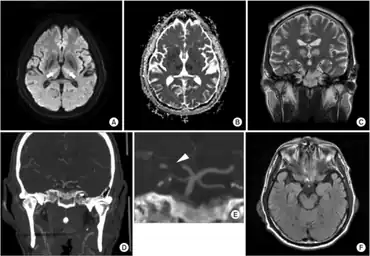

Diagnosis of pseudobulbar palsy is based on observation of the symptoms of the condition. Tests examining jaw jerk and gag reflex can also be performed. It has been suggested that the majority of patients with pathological laughter and crying have pseudobulbar palsy due to bilateral corticobulbar lesions and often a bipyrimidal involvement of arms and legs.[7] To further confirm the condition, MRI can be performed to define the areas of brain abnormality.